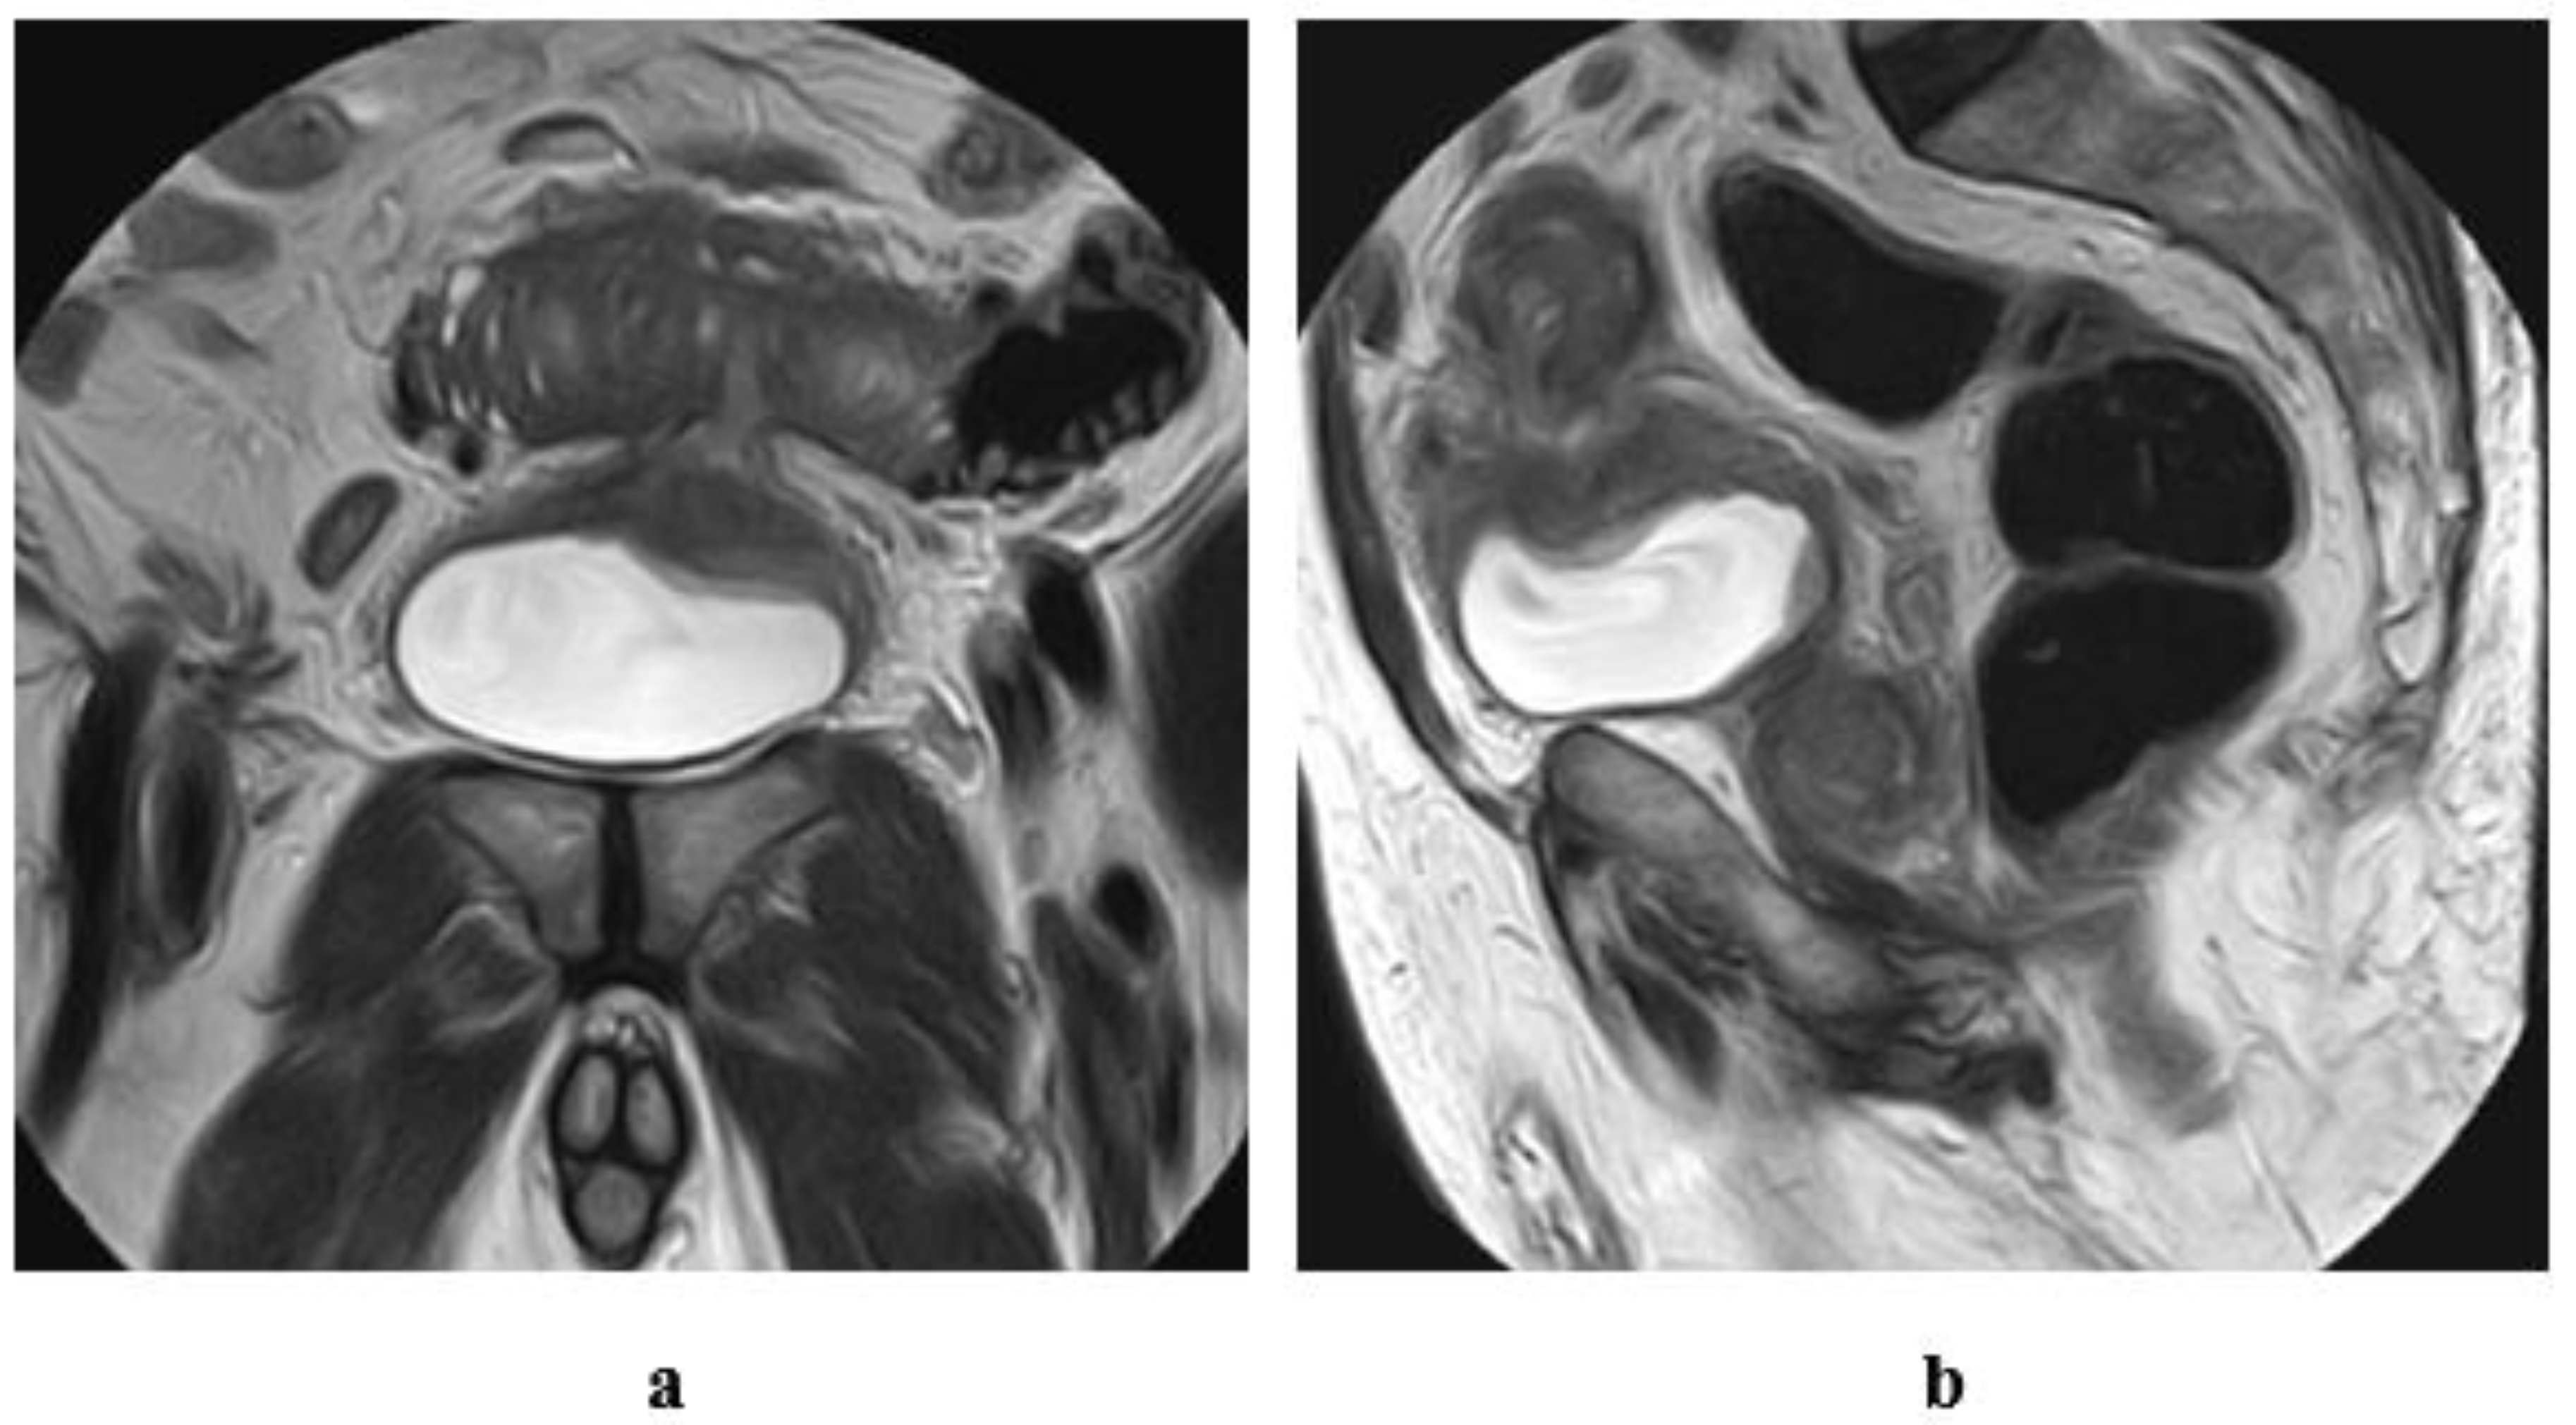

5. Ureterocele Urothelial Carcinoma

6. Mimics of Primary Urothelial Carcinoma

6.1. Neoplasms Mimicking Urothelial Carcinoma